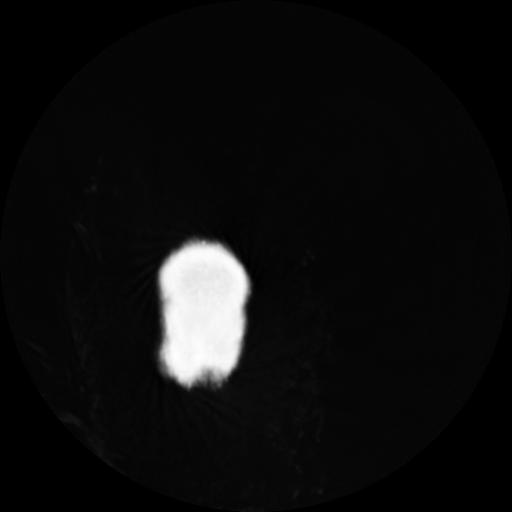

4 CEREBRO,,Vol,0.5,CEREBRO,,